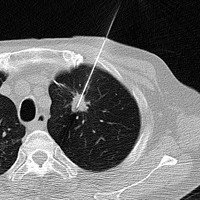

肺腫瘍や骨軟部腫瘍に対するラジオ波治療は我が国では保険診療が承認されていません。しかし、欧米からは手術と比べて低侵襲なラジオ波治療の報告が数多くなされています。本研究では、転移性肺癌、疼痛を伴う骨腫瘍(転移性骨腫瘍、類骨骨腫など)を中心に、CTによる画像誘導下にラジオ波治療を行い、その安全性と有効性を評価しています。